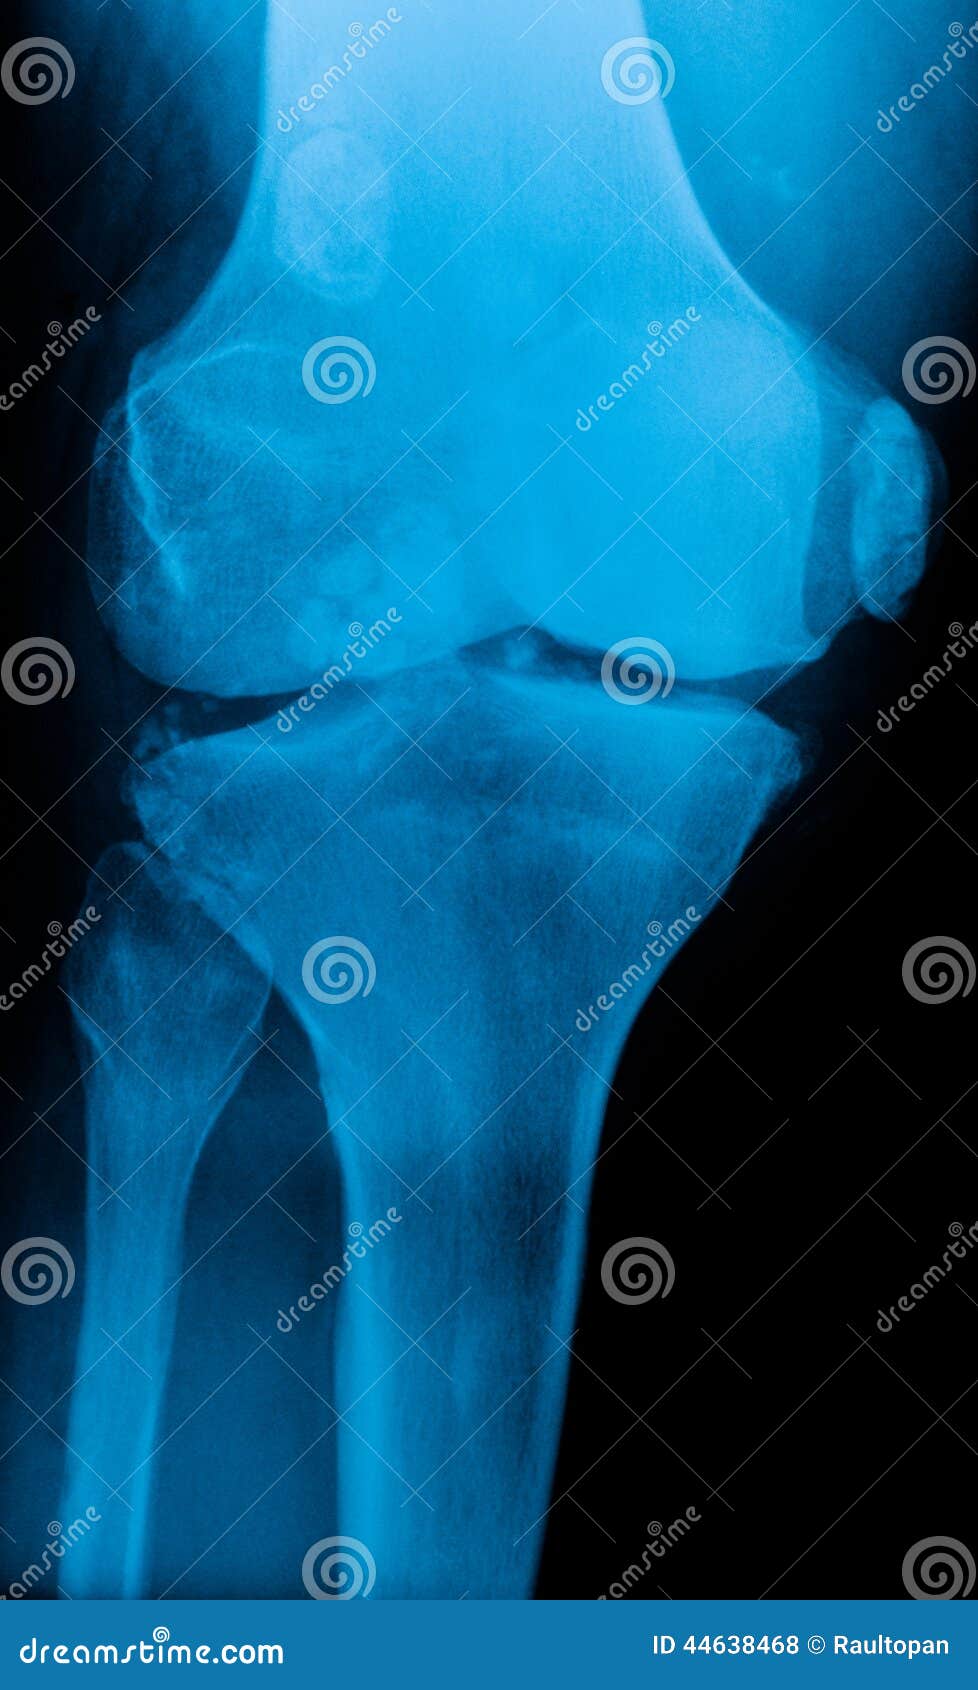

Knee xray stock photo. Image of carcass, elderly, cartilage 44638468 Oblique Knee X Ray Labeled The knee series is a set of radiographs taken to investigate knee joint pathology, often in the context of trauma. Rotate entire leg internally 45 degree. Aim 2.5cm distal to medial epicondyle. Align and center leg and knee to cr and to midline of table or ir. It usually comprises an ap and lateral projection, although. Normal adult knee seen. Oblique Knee X Ray Labeled.